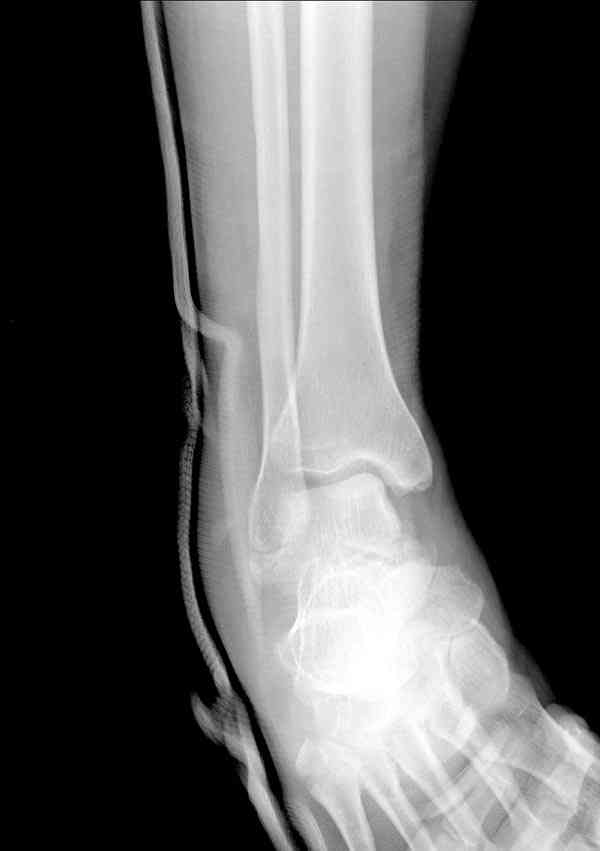

Решили не связываться с остеосинтезом, а сделать сразу берцово-пяточный блок. Снимки в приложении.

По завершении удлинения, наверно, заштифтуем.

Комментарии/критика приветствуются.